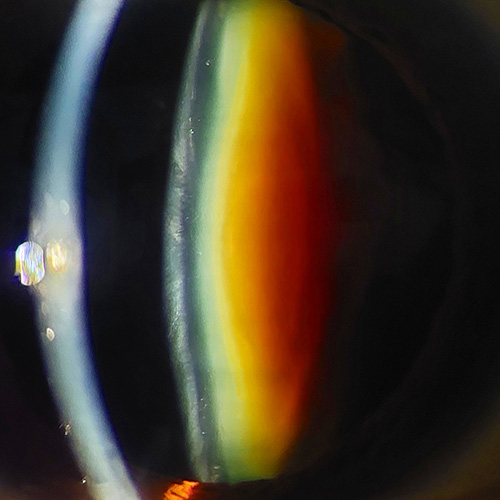

Alta especialidad en cirugía refractiva y córnea (APEC).

Alta especialidad en segmento anterior y cirugía de catarata (APEC).

Investigador en el área de cirugía de catarata y lentes intraoculares (multifocales premium).